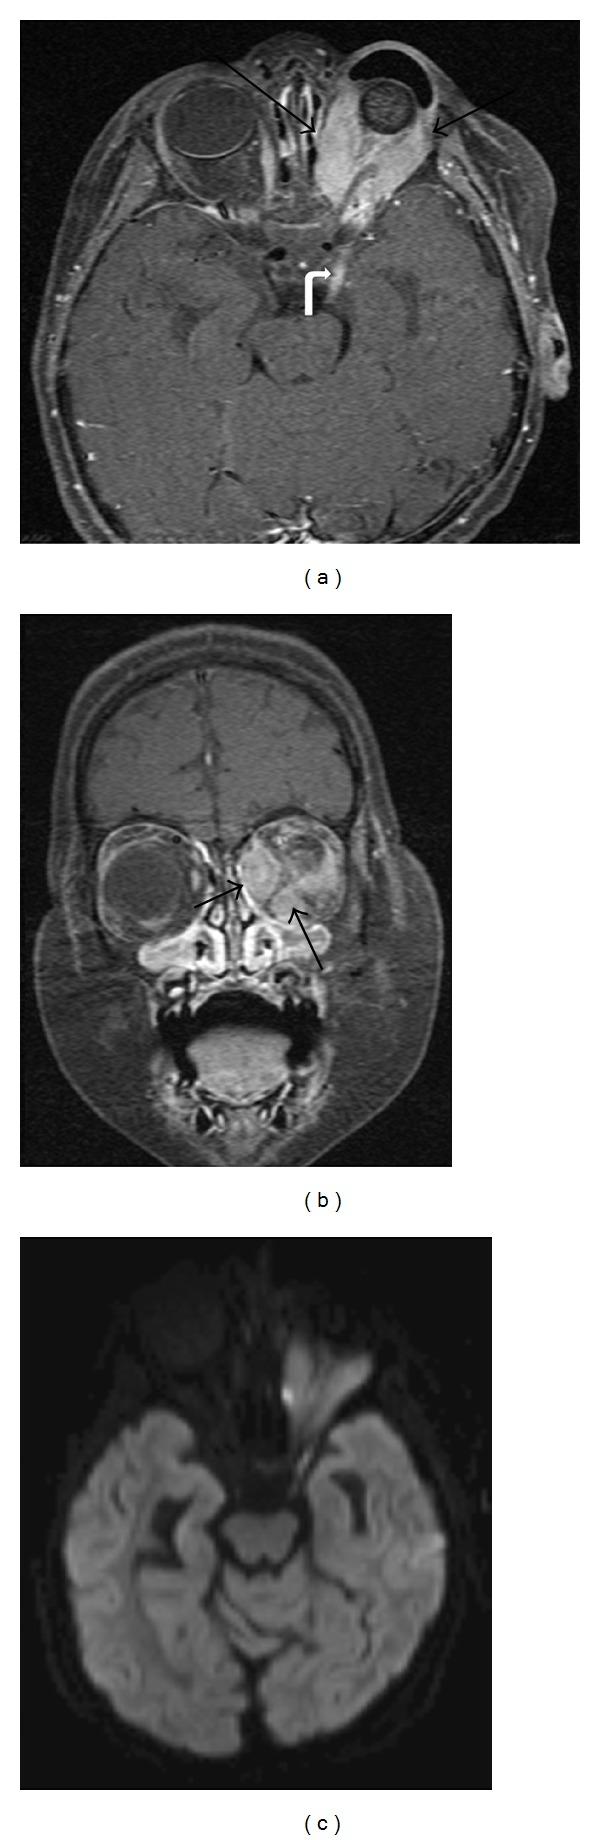

While pediatric orbital tumors are most often managed in tertiary care centers, clinicians should be aware of the signs of intraocular and orbital neoplasms. In the pediatric population, a delay in diagnosis of orbital and intraocular lesions, even if benign, can lead to vision loss and deformity. Intraocular lesions reviewed are retinoblastoma, medulloepithelioma, and retinal astrocytic hamartoma. Orbital neoplasms reviewed are rhabdomyosarcoma, neuroblastoma metastases, optic pathway glioma, plexiform neurofibroma, leukemia, lymphoprolipherative disease, orbital inflammatory syndrome, dermoid and epidermoid inclusion cysts, and Langerhans' cell histiocytosis. Vascular lesions reviewed are infantile hemangioma and venous lymphatic malformation. In conjunction with clinical examination, high-resolution ophthalmic imaging and radiologic imaging play an important role in making a diagnosis and differentiating between benign and likely malignant processes. The radiologic imaging characteristics of these lesions will be discussed to facilitate prompt diagnosis and treatment. The current treatment modalities and management of tumors will also be reviewed.

虽然儿科眼眶肿瘤多在三级医疗中心进行治疗,但临床医生应注意眼内和眼眶肿瘤的体征。在儿科人群中,即使是良性的眼眶和眼内病变的诊断延迟,也可能导致视力丧失和畸形。本文回顾了视网膜母细胞瘤、髓上皮瘤和视网膜星形细胞瘤等眼内肿瘤。眼眶肿瘤包括横纹肌肉瘤、神经母细胞瘤转移、视路胶质瘤、丛状神经纤维瘤、白血病、淋巴增生性疾病、眼眶炎症综合征、皮样和表皮样包涵囊肿以及朗格汉斯细胞组织细胞增生症。血管病变包括婴儿血管瘤和静脉淋巴管畸形。结合临床检查,高分辨率眼科成像和放射成像在做出诊断和区分良性和可能恶性过程方面发挥着重要作用。本文将讨论这些病变的放射成像特征,以促进快速诊断和治疗。还将回顾当前的治疗方法和肿瘤的管理。